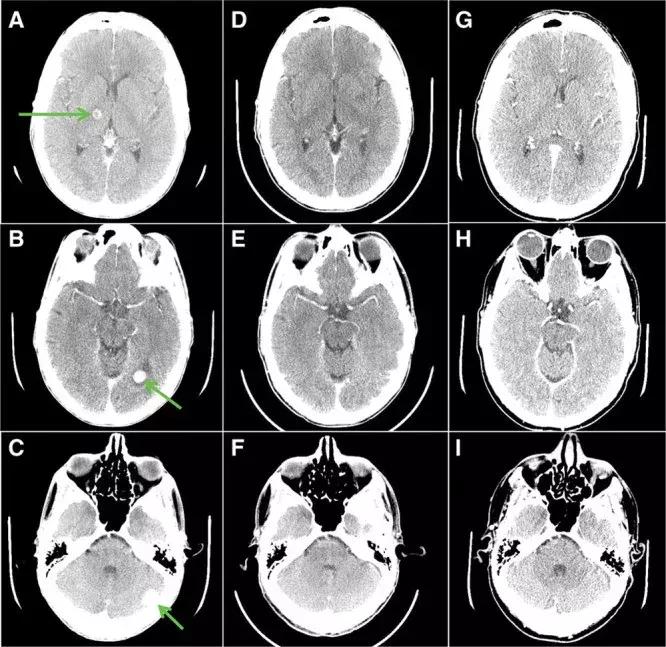

吃药前箭头指的都是肿瘤,20几个,吃药26天(DF)大部分消失, 吃药155 天(GI)肿瘤完全消失!

大叔每天以400 mg / ㎡口服,三周后,疼痛和呼吸困难症状消失,不在需要吸氧,并且,全身的肿瘤缩小46%,胸壁5公分的病灶已看不到摸不到!脑部肿瘤大部分消退;吃药5个月,症状不断改善,全身的肿瘤缩小77%,脑转移完全消失!!!